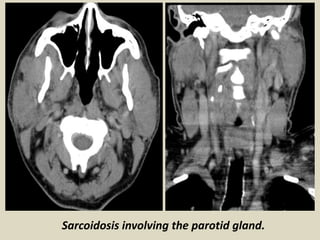

Sarcoidosis most commonly affects the salivary glands are rarely involved and usually manifests in

a variety of clinical patterns. They commonly presents as major salivary gland enlargement with only

histopathological involvement of the minor salivary glands. The second clinical pattern is characterized

by the absence of clinical salivary gland swelling with only histopathological involvement of minor

salivary glands. Parotid gland involvement occurs in 0.5-15 % of patients of sarcoidosis and may

manifest as unilateral or bilateral painless swelling.

Sarcoidosis involving the parotid gland.